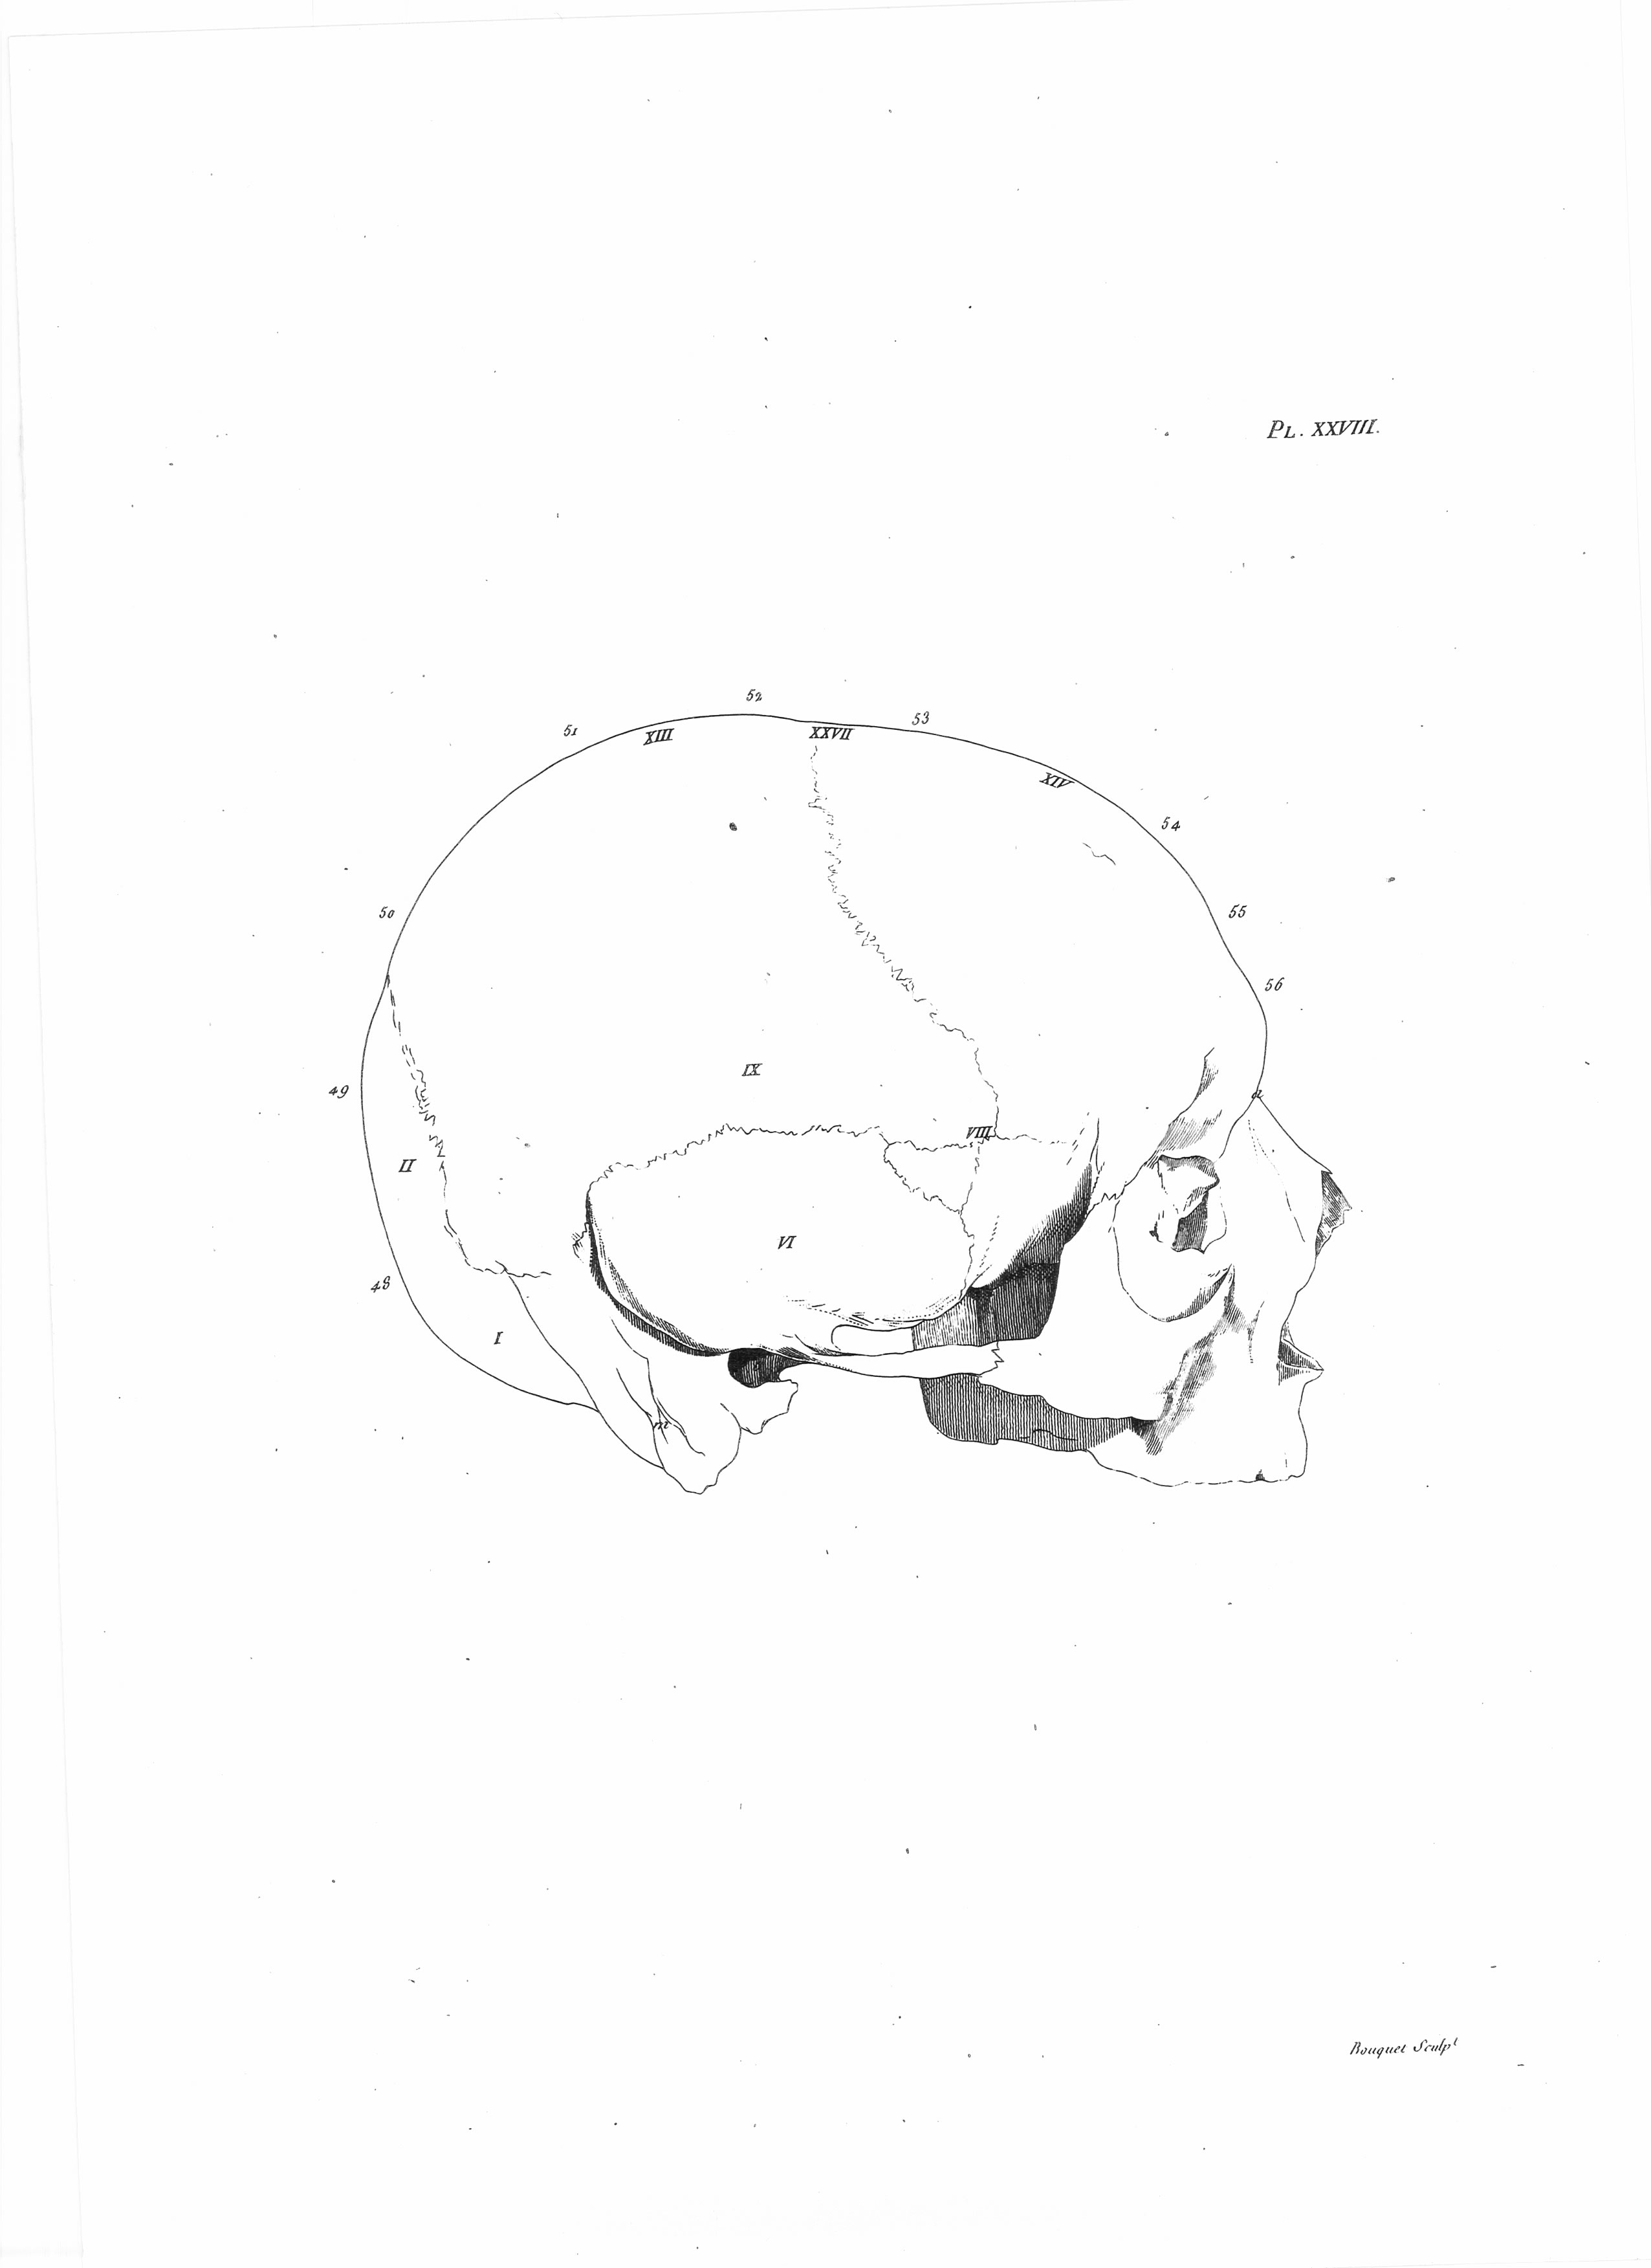

Gall, F. J. (1818). Anatomie et physiologie du système nerveux en général, et du cerveau en particulier, Avec des observations sur la possibilité de reconnoître plusieurs dispositions intellectuelles et morales de l´homme et des animaux, par la configuration de leurs têtes.

Librairie Grecque-Latine-Allemande, Vol. 3, I-XXXV u. 1-379 100 planches.